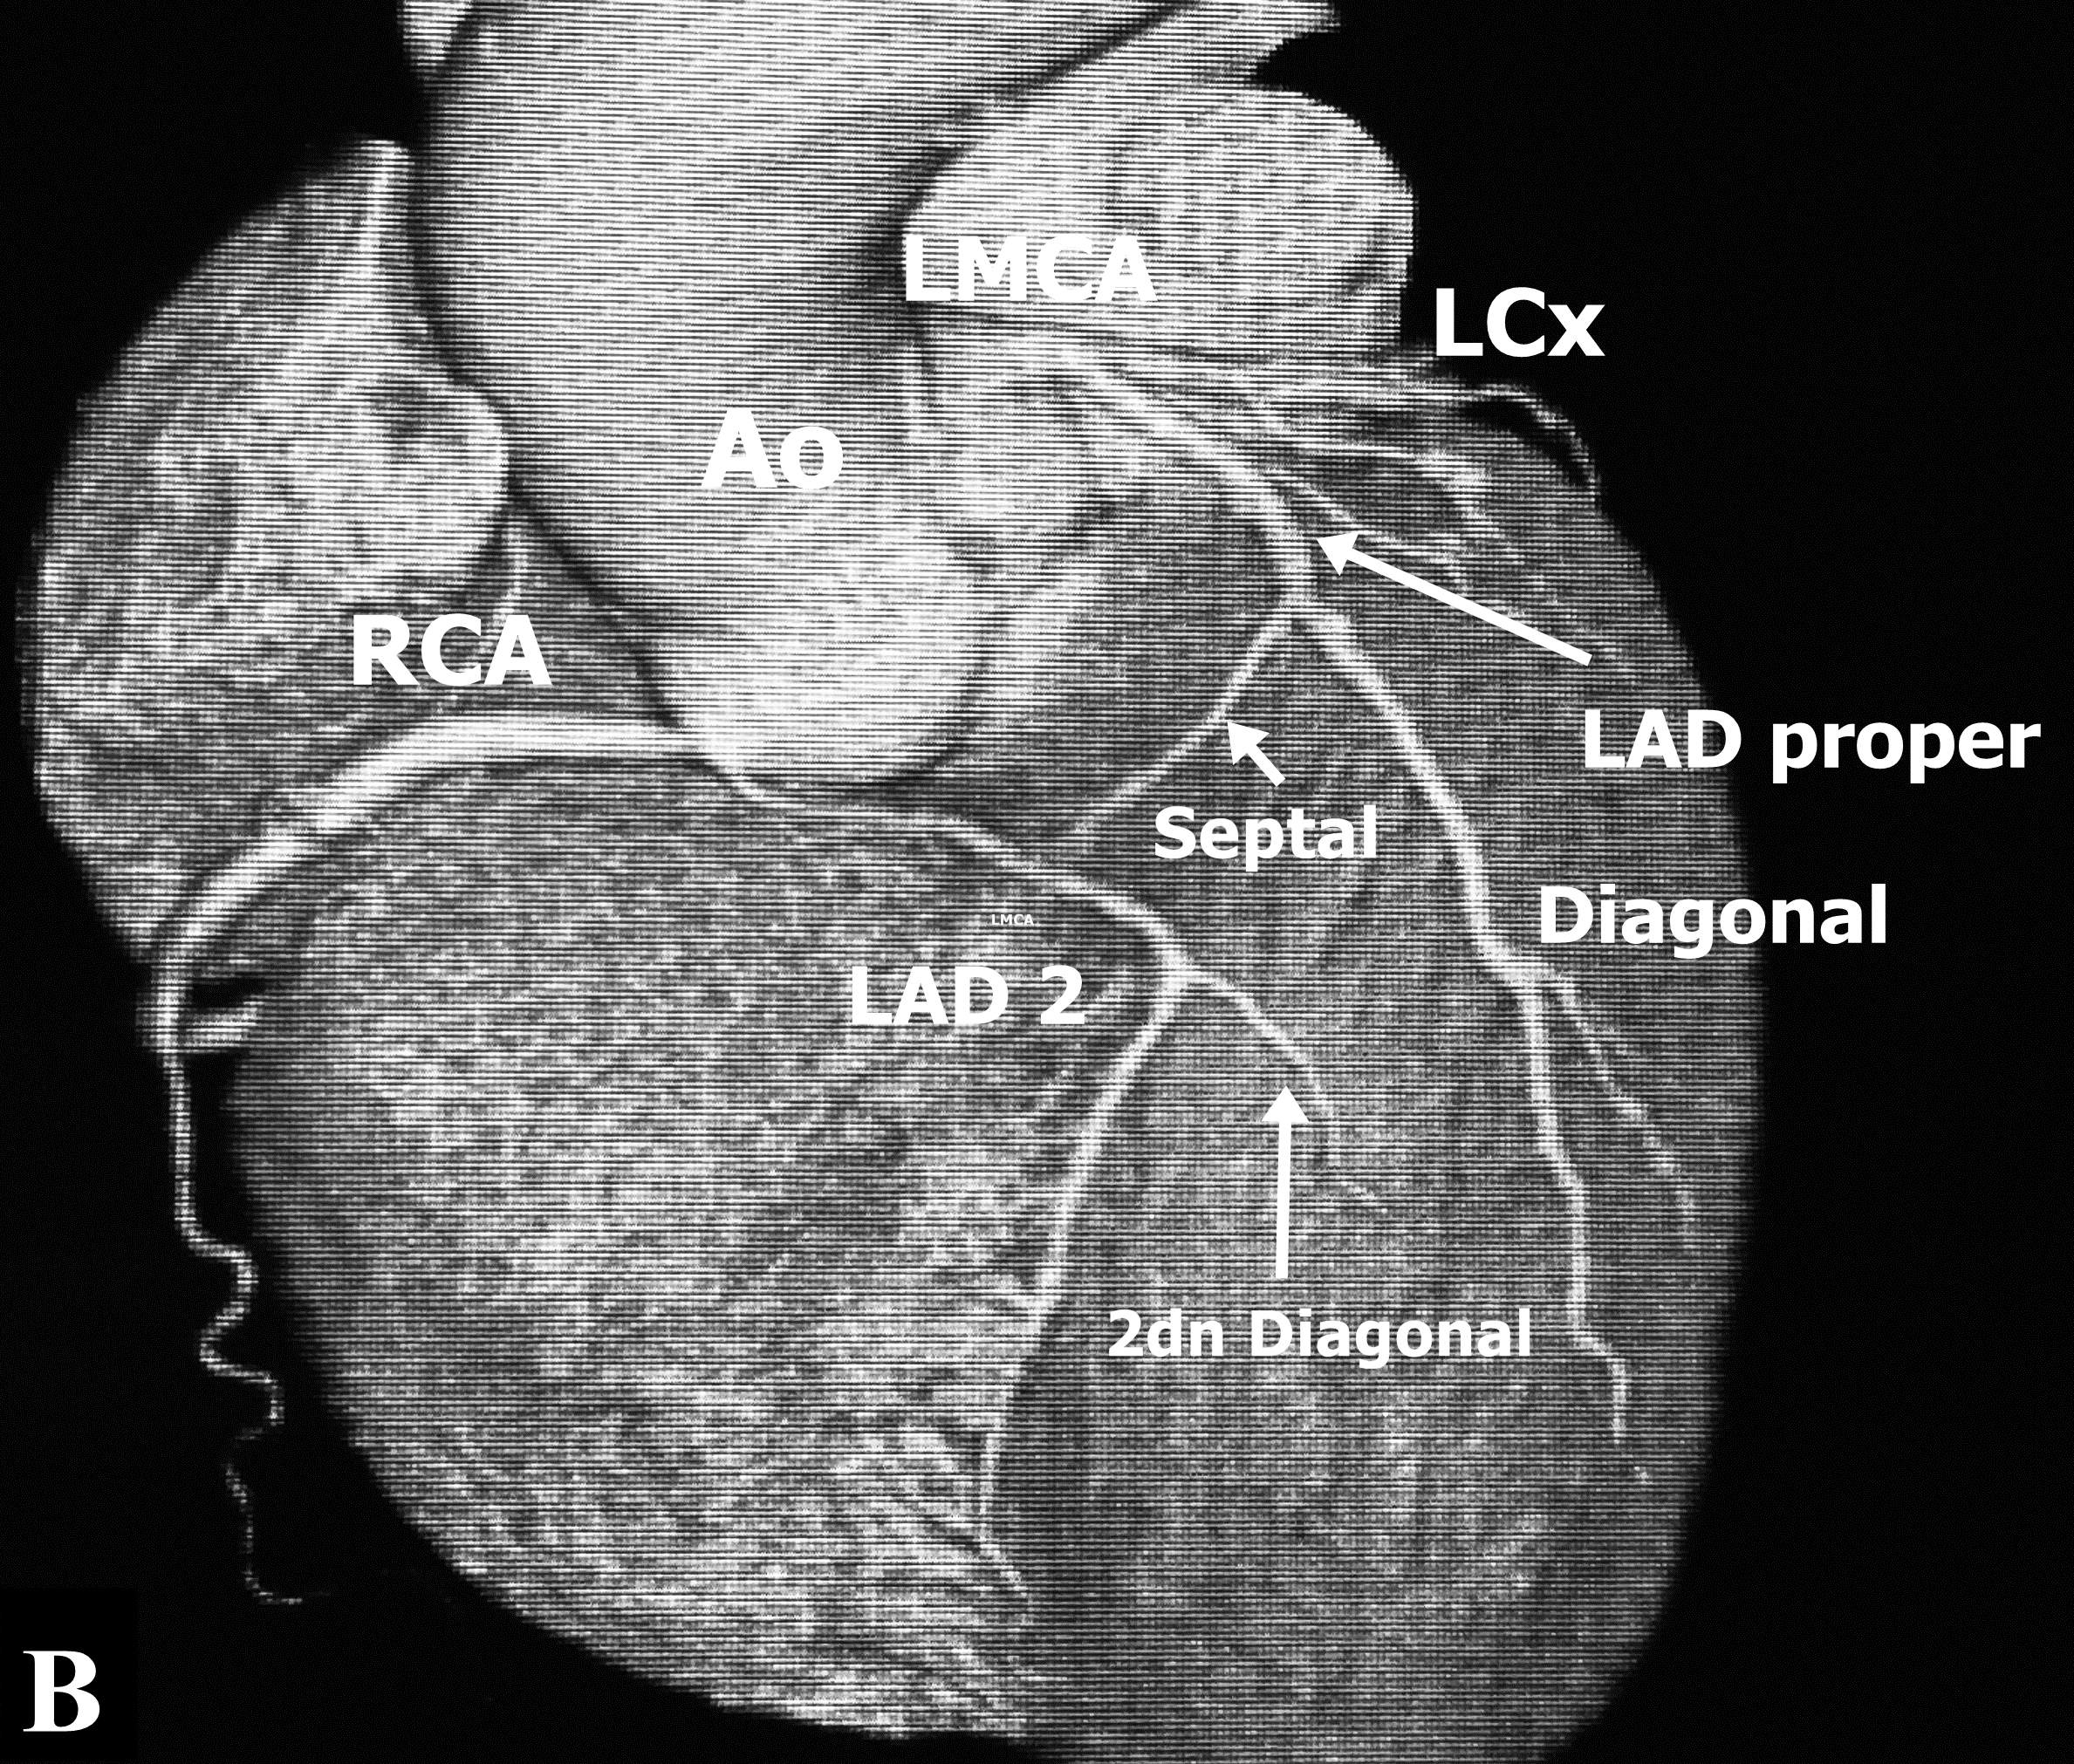

Figure 1: A. Angiographic view of Left Coronary Artery in RAO. LMCA: Left main coronary artery. LAD: Left anterior descending artery. LCx: Left circumflex artery. B. Right coronary artery in LCO. C. Angiographic view in LCO of Left coronary artery. LMCA: Left main coronary artery, LAD 1: Short Left descending artery, LCx: Left coronary artery. D. LAD 2: Long Left anterior descending artery, RCA: Right coronary artery.

Selective right coronary angiography revealed a dominant right coronary artery (RCA), without lesions (Figure 1B), during the injection, contrast media dyes unselectively an artery that comes very close to the origin of the RCA. Selective angiography of this vessel reveals that it is the middle - distal segment of the LAD which is directed right to left and return to its position on the AIVS giving a septal branch near its origin and a second diagonal branch (Figure 1D) establishing the diagnosis of a dual LAD system (Figure 1C), the proximal segment of the long LAD was narrower than the middle segment without an arteriosclerotic lesion and no compression was observed during systole. CT angiography identified the anomalous origin of long LAD from the Right Valsalva Sinus (RVS) near the origin of the RCA, and passing between the aortic root and RVOT providing a second diagonal branch without atherosclerotic lesions (Figure 2A&2B), and ending in the distal AIVS. The lesion in the posterolateral branch was successfully treated with the implant of 3.0 x 28 mm everolimus eluting stent.